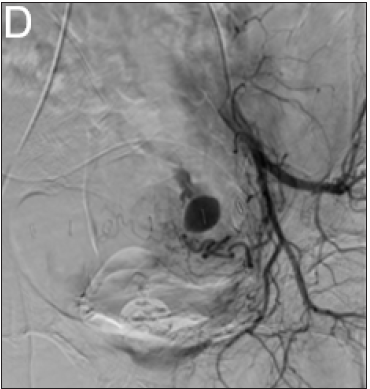

Two days after surgery, the patient presented a tympanic temperature of 38.6 °C but no symptoms other than chills. Then, the fever gradually subsided. At 7 days after surgery, the patient presented a tympanic temperature of 38.0 °C and no improvement in the pain in the lower abdominal and suprapubic area. Abdominalpelvic CT showed less than 5cm of localized air and fluid collection in the pelvic cavity and anterior abdominal wall (Figure 2). After walking back from the CT room, the patient suddenly complained of severe, sharp abdominal pain, and the volume in the JP drain was 70cc for an hour. TVUS did not produce any findings other minimal fluid collection in the cul-de sac. Once again, abdominal CT angiography was performed and revealed a pseudoaneurysm in the left pelvic cavity 1.5 cm in size with related bleeding but no rupture (Figure 3) and (Figure 4). Therefore, pelvic angiography (Figure 3) was performed for definitive diagnosis and treatment. It showed pseudoaneurysm formation at the side wall of the left uterine artery. Embolization was performed and occlusion of the artery was completed. A contralateral angiogram showed no communication with the lesion. Eight days after embolization, the JP drain was removed after, as there had been no fluid in the JP drain for three days, and the patient was discharged. At the 2-week follow-up, the patient was in good health.

Figure 4: Selective left uterine arteriogram confirming the diagnosis.